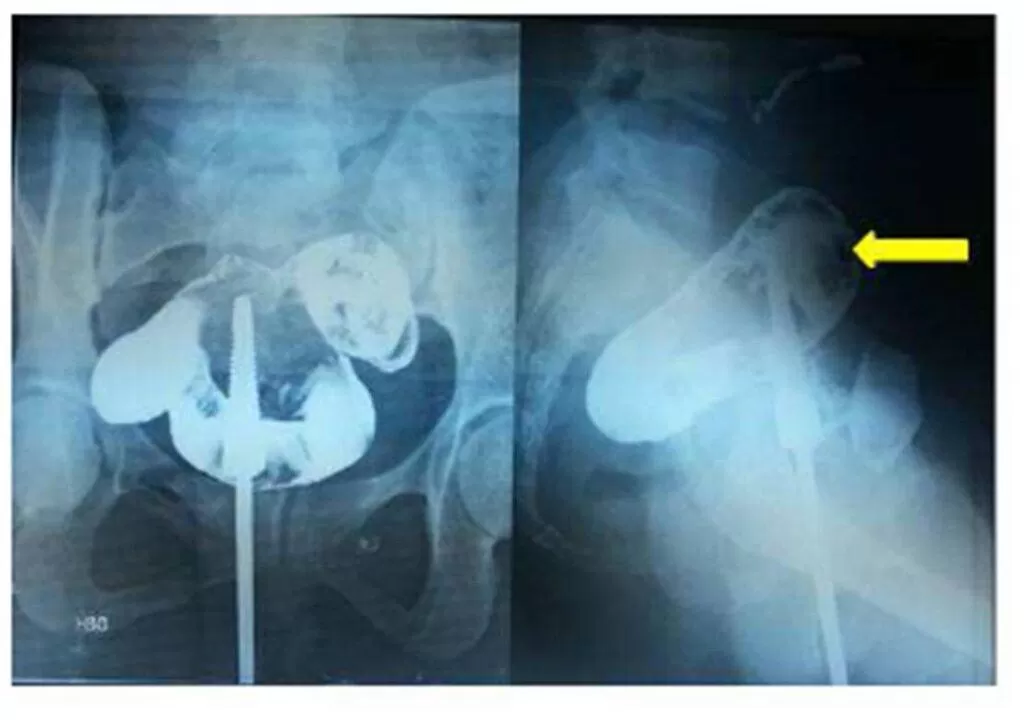

Exploratory laparotomy was performed and the sigmoid colon was found adherent to the anterior wall of the uterus (Fig.4).

Figure 4:  Sigmoid colon (black arrow) adherent to anterior surface of the uterus (white arrow).

Their separation demonstrated the fistulous opening in the sigmoid colon (Fig.5).The tract was excised along with resection of a small segment of sigmoid colon because of inflammation and scarring, and the continuity of the colon was restored. The internal os was dilated with Hegar dilator under visual guidance to relieve the cervical stenosis. The uterine wound was closed, and bilateral tubal ligation was performed. The post-operative period was uneventful and the patient has normal menses since then. The resected specimen of bowel sent for histopathology revealed the presence of tubercular disease.

Figure 5:  Opening of the fistula in the sigmoid colon (black arrow); the other end of the track  in the  uterus  being closed (white arrow).